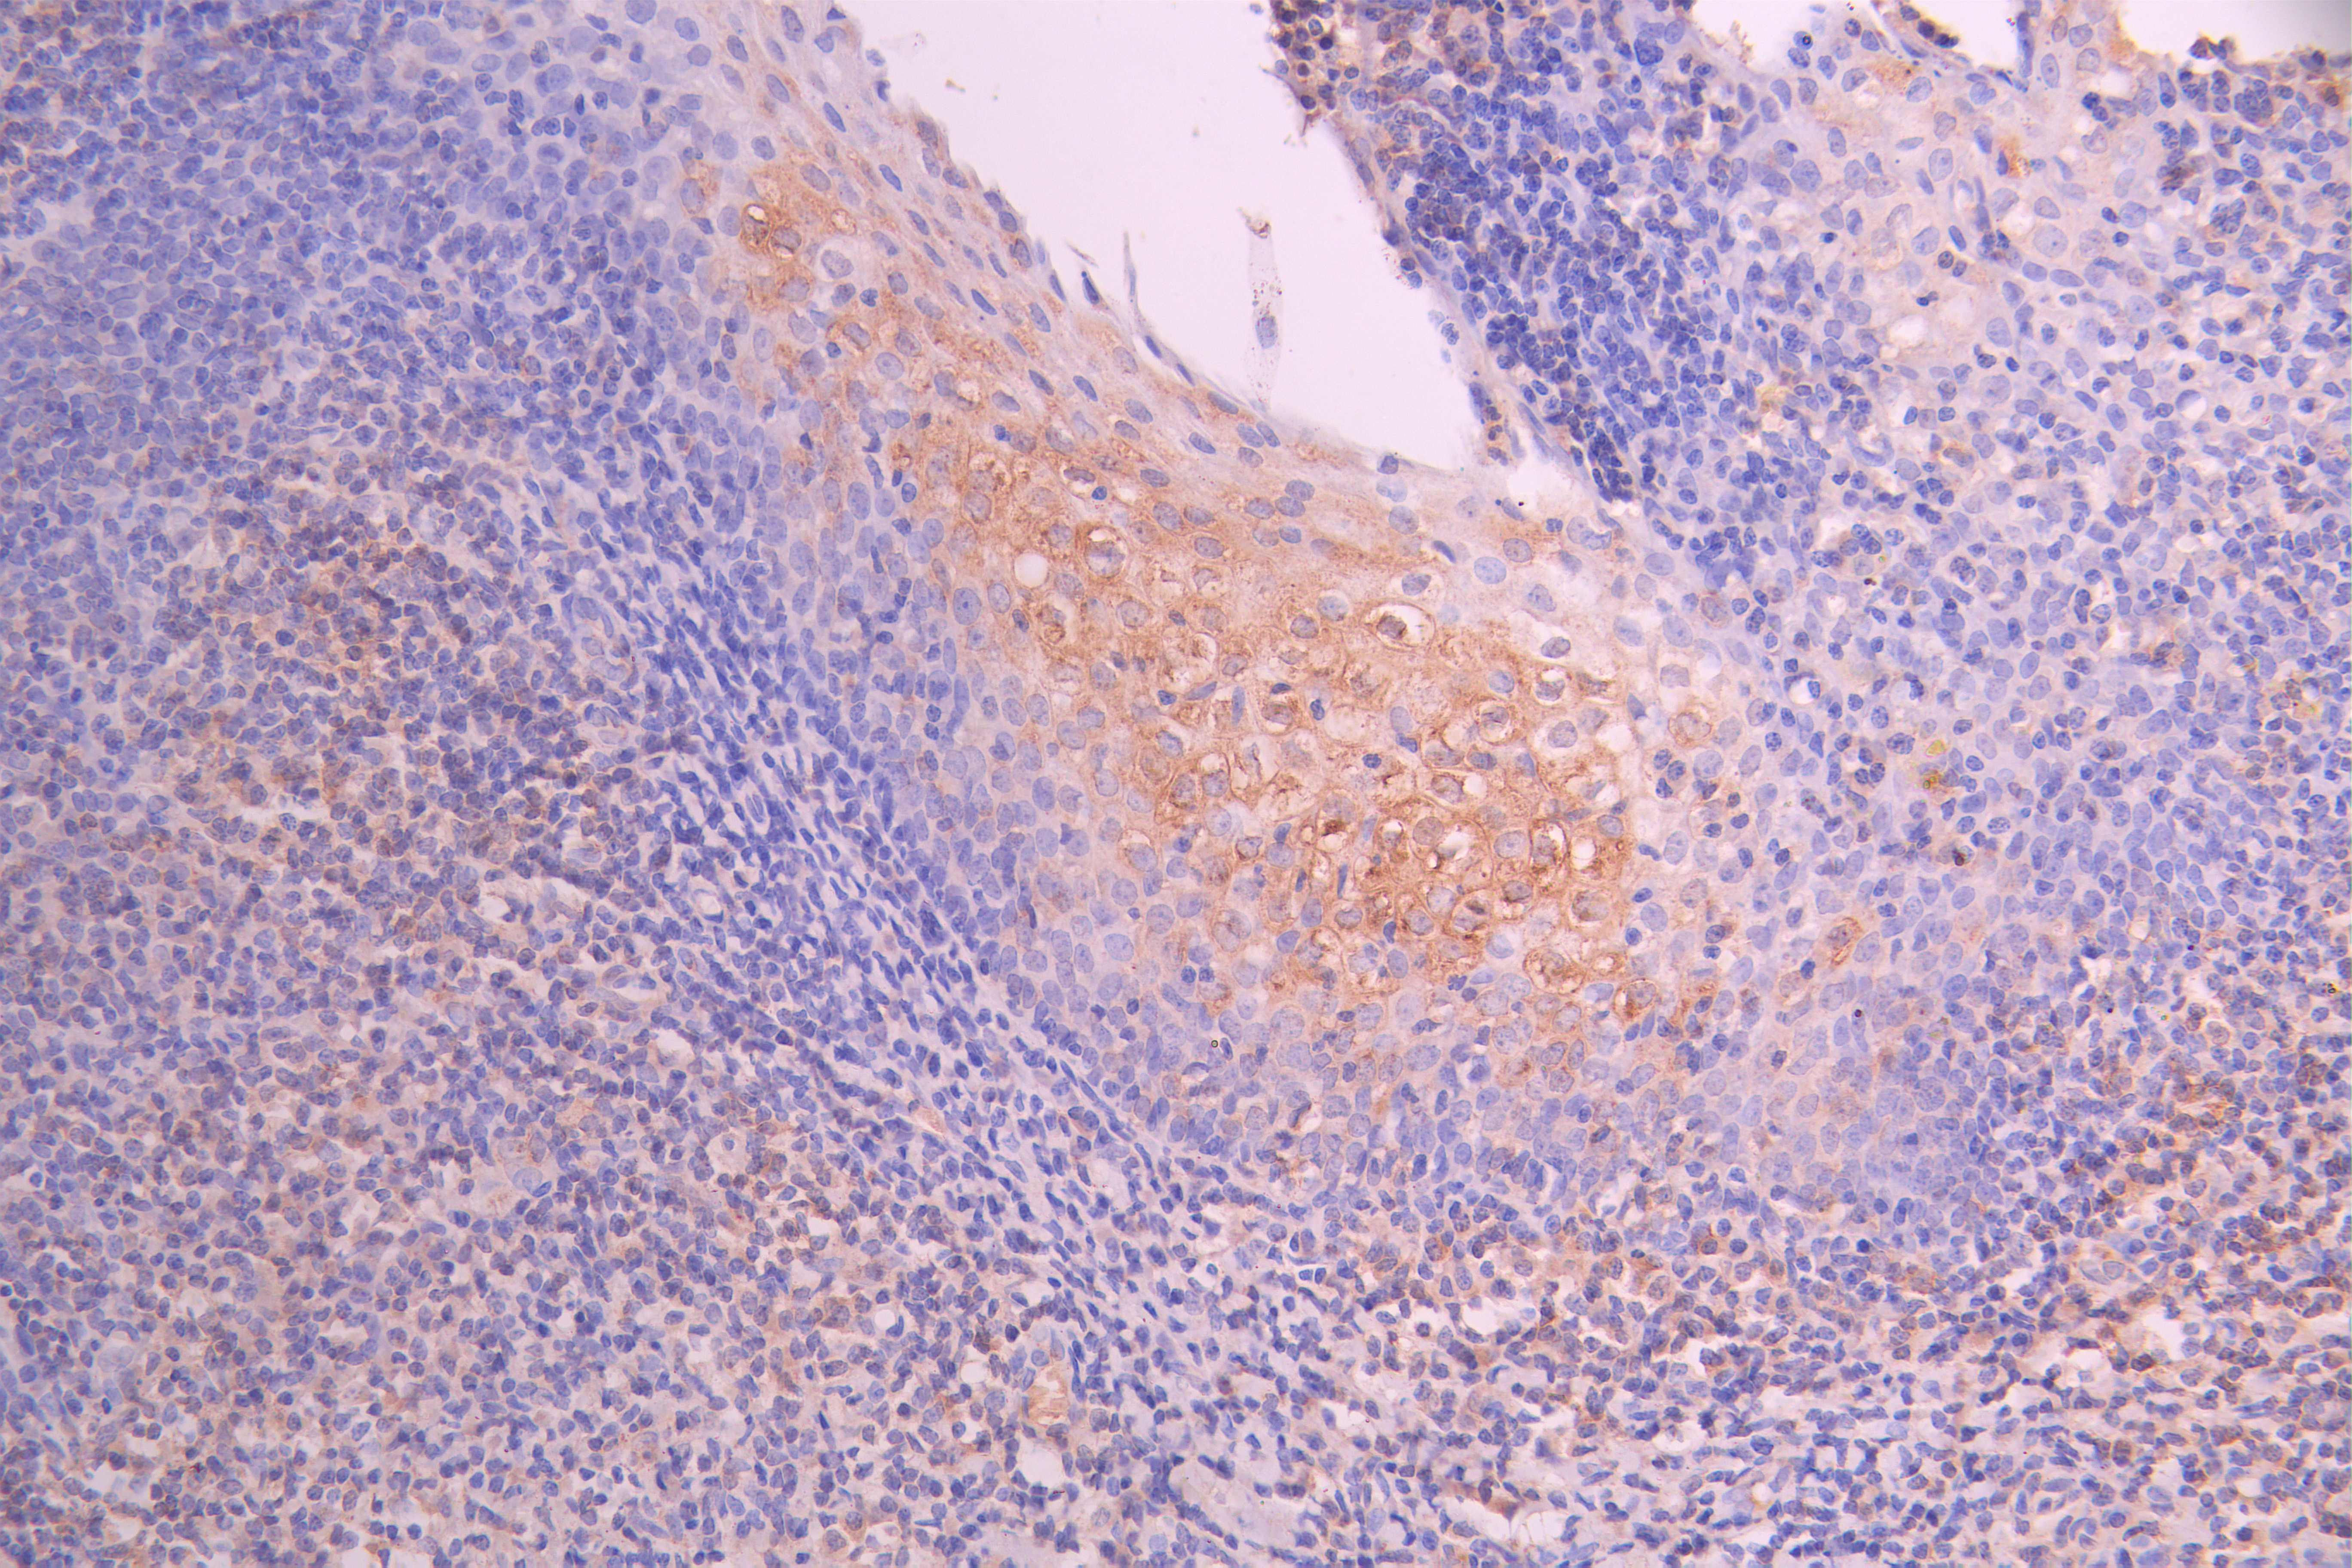

IHC image of CSB-RA822164MA1HU diluted at 1:50 and staining in paraffin-embedded human tonsil tissue performed on a Leica BondTM system. After dewaxing and hydration, antigen retrieval was mediated by high pressure in a citrate buffer (pH 6.0). Section was blocked with 10% normal goat serum 30min at RT. Then primary antibody (1% BSA) was incubated at 4°C overnight. The primary is detected by a Anti-Human lgG, Fcy Fragment Specific labeled by HRP and visualized using 0.05% DAB.